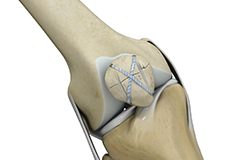

The knee is a complex joint of the body that is vital for movement. The four major ligaments of the knee are anterior cruciate ligament (ACL), posterior cruciate ligament (PCL), medial collateral ligament (MCL) and lateral collateral ligament (LCL).

Multiligament Instability

Injury to more than one knee ligament is called a complex or multiligament knee injury and may occur during sports or other physical activities.

Multiligament Knee Injuries